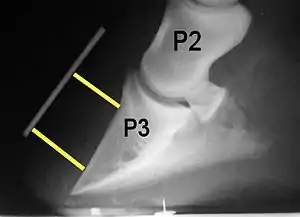

Rotation is the most common form of displacement, and, in this case, the tip of the coffin bone rotates downward.[4] The degree of rotation may be influenced by the severity of the initial attack and the time of initiation and aggressiveness of treatment. A combination of forces (e.g. the tension of the deep digital flexor tendon and the weight of the horse) result in the deep digital flexor tendon literally pulling the dorsal face of the coffin bone away from the inside of the hoof wall, which allows the coffin bone to rotate. Also, ligaments attaching the collateral cartilages to the digit, primarily in the palmar portion of the foot, possibly contribute to a difference in support from front to back. The body weight of the animal probably contributes to rotation of the coffin bone. Rotation results in an obvious misalignment between PII (the short pastern bone) and PIII (the coffin bone). If rotation of the third phalanx continues, its tip can eventually penetrate the sole of the foot.

Several radiographic measurements, made on the lateral view, allow for objective evaluation of the episode.

- Coronary extensor distance (CE): the vertical distance from the level of the proximal coronary band to the extensor process of P3. It is often used to compare progression of the disease over time, rather than as a stand-alone value. A rapidly increasing CE value can indicate distal displacement (sinking) of the coffin bone, while a more gradual increase in CE can occur with foot collapse. Normal values range from 0–30 mm, with most horses >12–15 mm.[1]

- Sole depth (SD): the distance from the tip of P3 to the ground.

- Digital breakover (DB): distance from the tip of P3 to the breakover of the hoof (dorsal toe).[1]

- Palmar angle (PA): the angle between a line perpendicular to the ground, and a line at the angle of the palmar surface of P3.

- Horn:lamellar distance (HL): the measurement from the most superficial aspect of the dorsal hoof wall to the face of P3. 2 distances are compared: a proximal measurement made just distal to the extensor process of P3, and a distal measurement made toward the tip of P3. These two values should be similar. In cases of rotation, the distal measurement will be higher than the proximal. In cases of distal displacement, both values will increase, but may remain equal. Therefore, it is ideal to have baseline radiographs for horses, especially for those at high-risk for laminitis, to compare to should laminitis ever be suspected. Normal HL values vary by breed and age:[1]